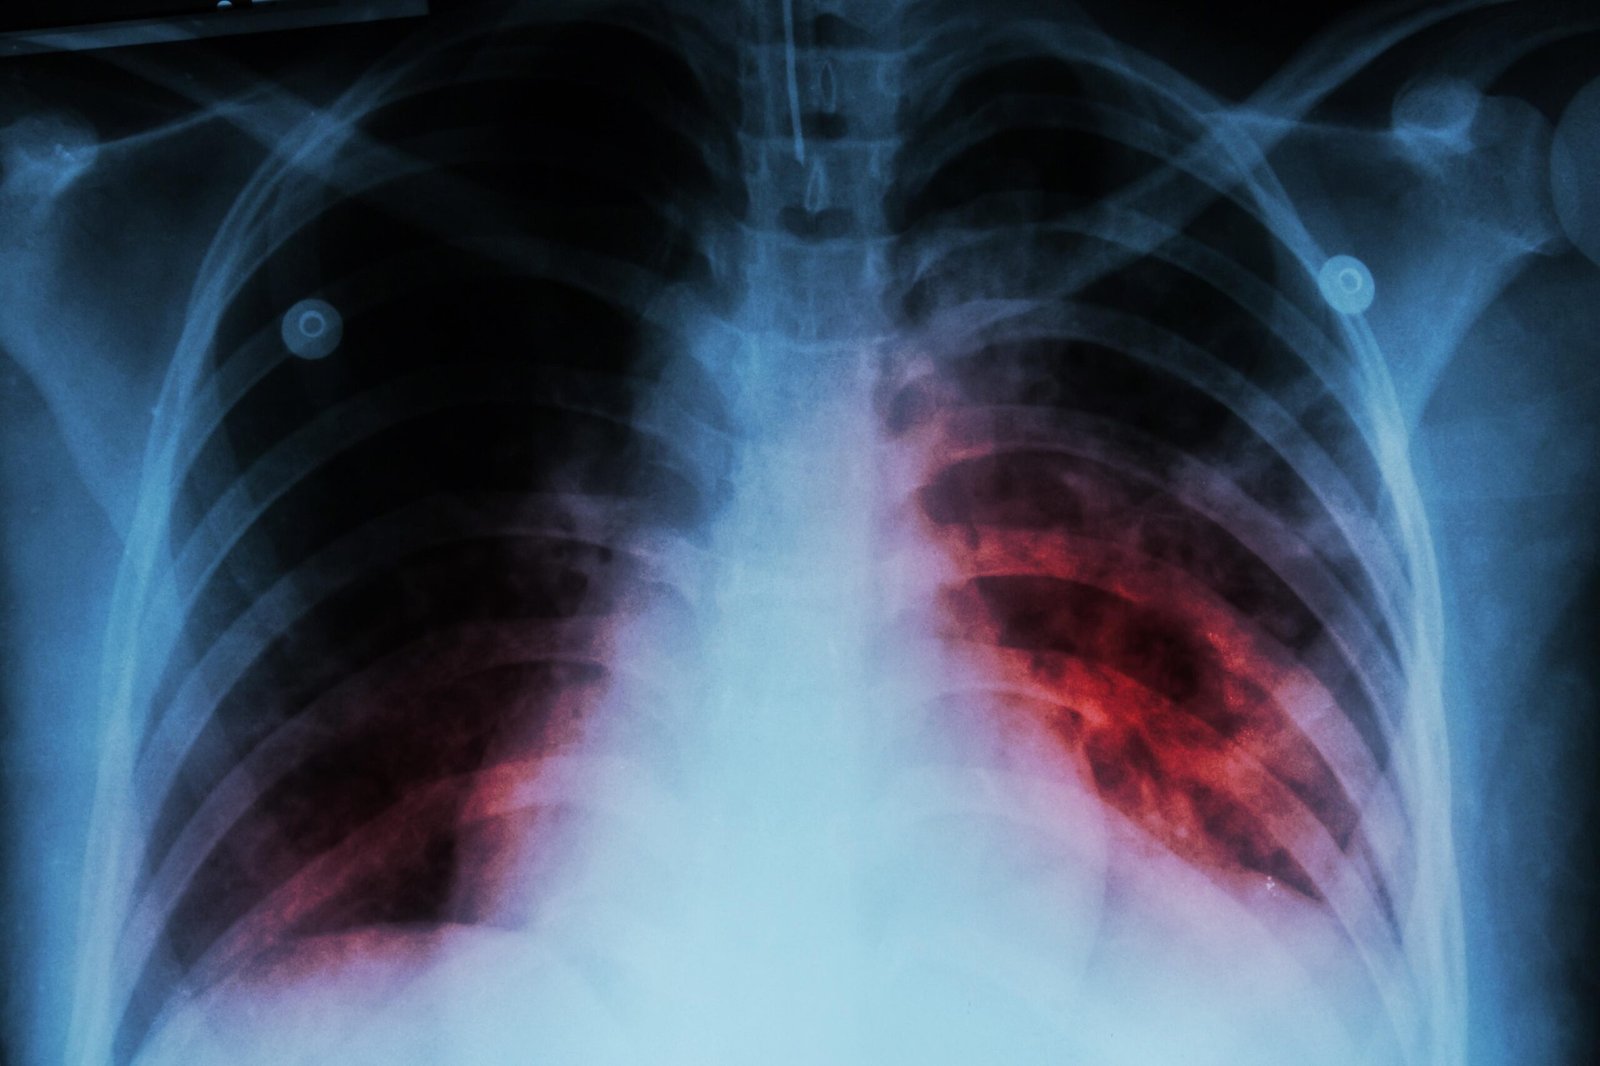

En cuanto a la detección, señaló que los estudios de expectoración permiten confirmar el diagnóstico en un periodo aproximado de 24 horas, complementados con estudios de imagen. Añadió que, en algunos casos, el antecedente de convivencia con personas infectadas resulta clave para la identificación oportuna.